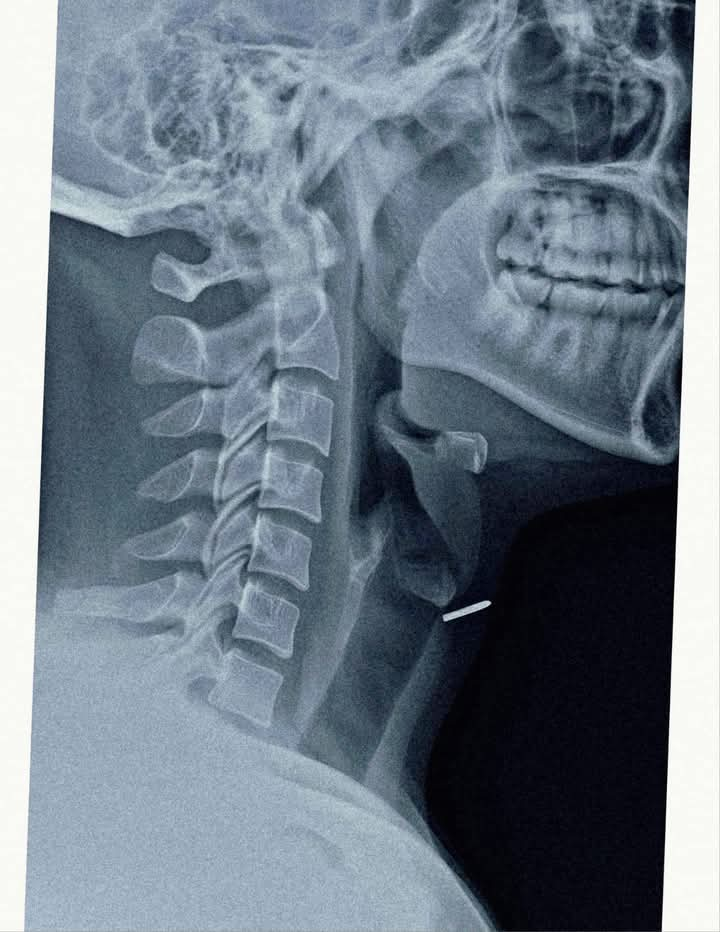

आधुनिक कील लगाने वाली मशीन के खराब होने से हुआ हादसा* लखीमपुर-खीरी। तकनीक जितनी सहायक होती है, कभी-कभार एक चूक से उतनी ही घातक व जानलेवा भी हो जाती है। महेवागंज में एक ऐसा ही मामला सामने आया है जहां फर्नीचर बनाने वाले कारपेंटर के साथ ऐसा ही खतरनाक हादसा हुआ, जब वह एक स्वचालित कील लगाने वाली मशीन से काम कर रहा था। अचानक मशीन में खराबी आ गई और एक कील तेज़ी से उल्टी दिशा में चलकर उसकी गर्दन में घुस गई घायल युवक दीपू (28) को स्वशासी राजकीय चिकित्सा महाविद्यालय संबद्ध जिला अस्पताल मोतीपुर ओयल लाया गया। मरीज पहले से एक्स रे करा कर लाया था, जांच करने में पता चला कि कील सीधी थायरॉइड ग्रंथि में जाकर फंस गई है और श्वास नली के ठीक पास स्थित है। यह स्थिति अत्यंत गंभीर थी क्योंकि थोड़ी सी भी लापरवाही जानलेवा साबित हो सकती थी इस संवेदनशील स्थिति को गंभीरता से लेते हुए सहायक आचार्य ईएनटी सर्जन डॉ. मनोज शर्मा ने लोकल एनेस्थीसिया में ऑपरेशन किया और कील को सफलतापूर्वक सर्जरी कर बाहर निकाला। ऑपरेशन के बाद मरीज की स्थिति पूरी तरह सामान्य रही और उसे उसी दिन अस्पताल से छुट्टी दे दी गई। साथ ही किसी तरह की समस्या होने पर तत्काल दिखाने के लिए एडवाइस किया गया है डॉ. शर्मा ने बताया कि यह मामला दुर्लभ और चुनौतीपूर्ण था। “कील श्वसन नली के बेहद नज़दीक थी। हमें अत्यधिक सावधानी बरतनी पड़ी ताकि कील निकालते समय कहीं श्वास नली में ना चली जाए” प्रधानाचार्य डॉ वाणी गुप्ता ने बताया कि इस घटना ने यह साबित कर दिया कि तकनीक का इस्तेमाल करते समय पूरी सावधानी बरतनी चाहिए, जहाँ तक हो सके स्वचालित मशीनों को इस्तेमाल करते समय सुरक्षा उपकरण जरूर पहनें। किसी भी प्रकार की दुर्घटना होने पर तत्काल नजदीकी स्वास्थ्य केंद्र पर पहुंचे। सीएमएस डॉ आरके कोली ने बताया कि किसी भी दुर्घटना के बाद किसी की जान बचाने के लिए “समय” सबसे महत्वपूर्ण कारक है, समय रहते मरीज को अस्पताल पहुंचने से चिकित्सकों को स्थित अति गंभीर नहीं होती है और अधिकतर मामलों मे मरीज की जान बचायी जा सकती है। जिला अस्पताल एवं हमारा स्टाफ हर समय किसी भी प्रकार की दुर्घटनाओं ने निपटने के लिए तैयार रहता है।